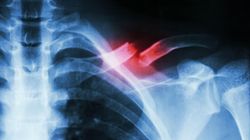

niepełny zakres ruchu ból